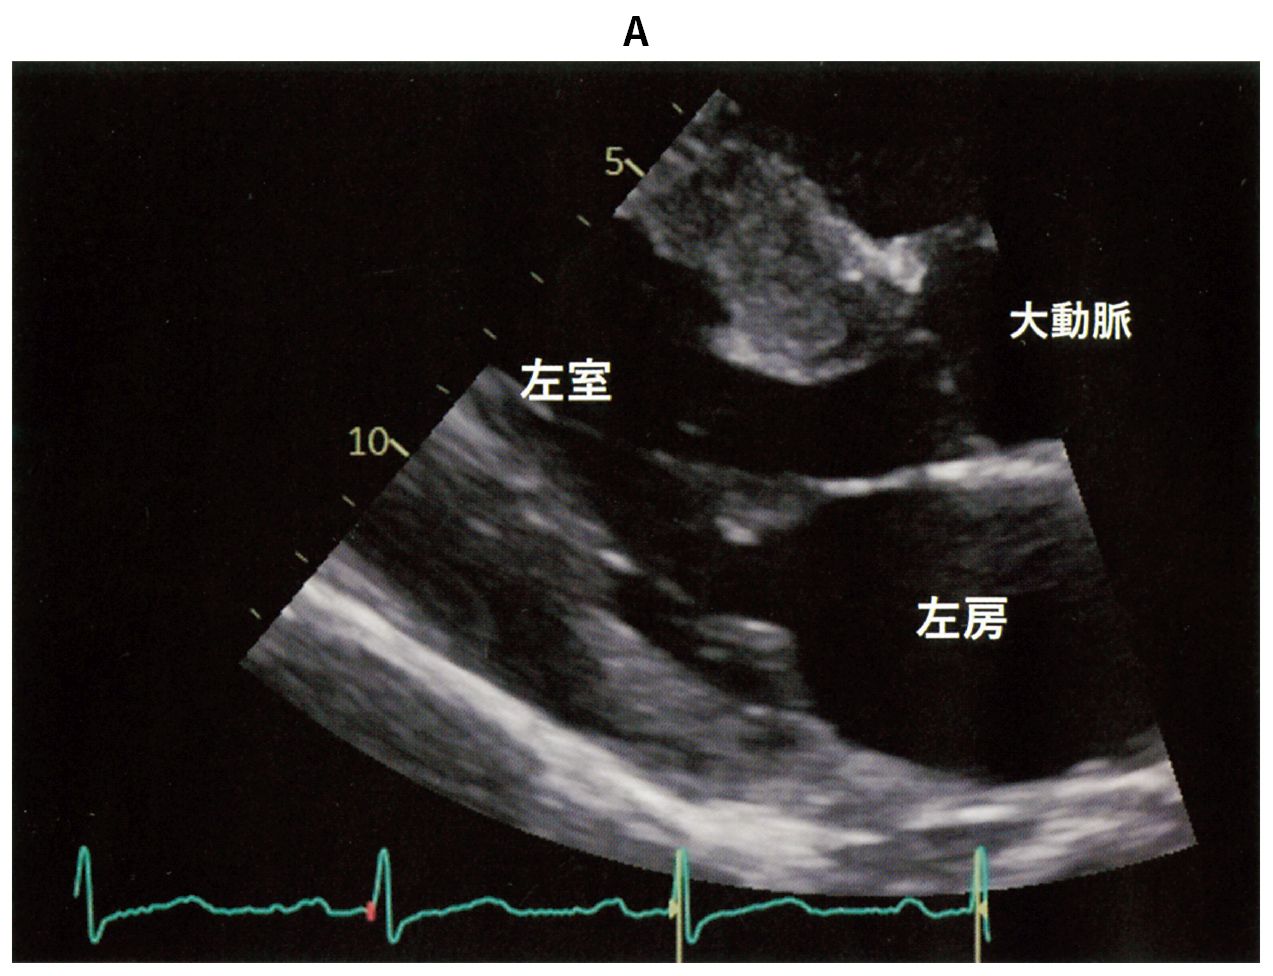

54歳の男性。労作時の息切れを主訴に来院した。以前から心電図異常を指摘されていたが精査は受けていなかった。身長172cm,体重64kg。体温36.5℃。脈拍72/分,整。血圧130/80mmHg。呼吸数18/分。頸静脈の怒張は認めない。胸骨左縁第4肋間を中心にLevine 4/6の収縮期雑音とⅣ音を聴取する。呼吸音に異常を認めない。腹部は平坦,軟で,肝・脾を触知しない。下肢に浮腫を認めない。心エコー検査の傍胸骨長軸像(A)とMモード(B)とを下に示す。